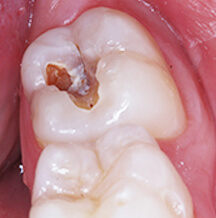

- Dental Caries is the teeth infection that result in dissolution and destruction of the calcified tissues of the tooth structure.

- It is essential to understand that cavitations in teeth (destruction of tooth surface,creating a ''CAVITY''or defect) are signs of bacterial infection.

- Carious lesions occur under a mass of bacteria capable of producing a sufficiently acidic environment to demineralize tooth structure.

- A gelatinous mass of bacteria adhering to the tooth surface is termed Dental Plaque.This plaque bacteria metabolize refined carbohydrates for energy and produce organic acids as a by-product.

- These acids may cause a carious lesion by dissolution of the tooth's crystalline structure.

- The main bacteria's involved in information of CAVITIS in the mouth are namely Streptococcus mutans serotypes.